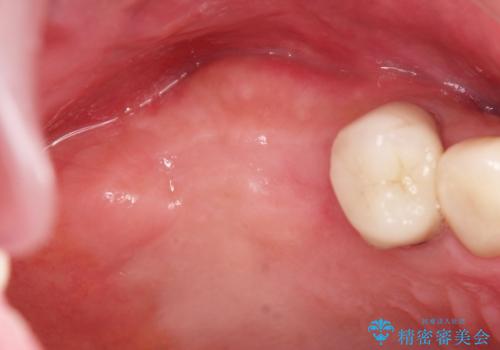

- 歯を抜いたまま放置してしまい、「やはりしっかりと噛めるような状態にしてほしい」とインプラント治療を希望され来院されました。

人工歯根であるインプラントを埋入することで奥歯でまたしっかりと噛める咬合機能を回復します。